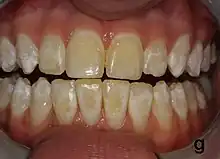

It appears as a range of visual changes in enamel[4] causing degrees of intrinsic tooth discoloration, and, in some cases, physical damage to the teeth. The severity of the condition is dependent on the dose, duration, and age of the individual during the exposure.[1] The "very mild" (and most common) form of fluorosis, is characterized by small, opaque, "paper white" areas scattered irregularly over the tooth, covering less than 25% of the tooth surface. In the "mild" form of the disease, these mottled patches can involve up to half of the surface area of the teeth. When fluorosis is moderate, all of the surfaces of the teeth are mottled and teeth may be ground down and brown stains frequently "disfigure" the teeth. Severe fluorosis is characterized by brown discoloration and discrete or confluent pitting; brown stains are widespread and teeth often present a corroded-looking appearance.[1]

The adequate diagnosis of fluorosis can be diagnosed by visual clinical examination. This requires inspection of dry and clean tooth surfaces under a good lighting.[6] There are individual variations in clinical fluorosis manifestation which are highly dependent on the duration, timing, and dosage of fluoride exposure.There are different classifications to diagnose the severity based on the appearances. The clinical manifestation of mild dental fluorosis is mostly characterised a snow flaking appearance that lack a clear border, opaque, white spots, narrow white lines following the perikymata or patches as the opacities may coalesce with an intact, hard and smooth enamel surface on most of the teeth.[7] With increasing severity, the subsurface enamel, all along the tooth becomes more porous. Enamel may appear yellow/ brown discolouration and/ or many and pitted white-brown lesions that look like cavities. They are often described as "mottled teeth".[8] Fluorosis does not cause discolouration to the enamel directly, as upon eruption into the mouth, affected permanent teeth are not discoloured yet. In dental enamel, fluorosis causes subsurface porosity or hypomineralizations, which extend toward the dentinal-enamel junction as the condition progresses and the affected teeth become more susceptible to staining. Due to diffusion of exogenous ions (e.g., iron and copper), stains develop into the increasingly and abnormally porous enamel.[7]